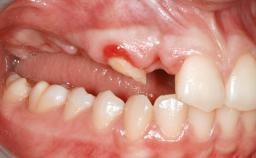

A 47-year-old woman who had suffered from aggressive periodontitis requiring a number of periodontal interventions over more than 10 years was referred by her general dental practitioner and periodontologist for bone augmentation and implant therapy. Her failing dentition had already been scheduled for extraction. The patient expressed a desire for implant-supported fixed restorations and esthetic improvement of her lower face. She had agreed to consult with a maxillofacial surgeon after the referring dentist had suggested bone augmentation. An initial examination by the maxillofacial surgeon revealed mobility of all residual teeth in a patient who was very unhappy with the function of her removable partial dentures. Due to periodontally migrated flaring teeth and loss of occlusal support, the vertical dimension of occlusion was dramatically reduced. The patient was displeased with her lower face because of deepened nasolabial, commissural, and supramental folds.

Bone Volume Horizontally and vertically sufficient Horizontally deficient Deficient vertically or deficient vertically AND horizontally

Bone Volume Deficient vertically or deficient vertically AND horizontally